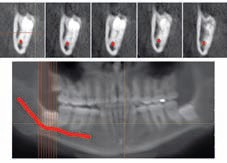

Coronectomie verstandskies